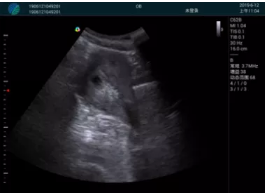

M20查看:囊內(nèi)回聲均勻,邊界清晰,囊壁光滑

M20引導(dǎo)抽吸術(shù)后囊腫消失,原區(qū)域空腔形成,脂肪層與腺體層架構(gòu)發(fā)生改變